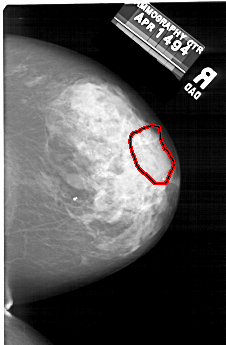

FILE: A_2000_1.RIGHT_MLO.OVERLAY

TOTAL_ABNORMALITIES 1

ABNORMALITY 1

LESION_TYPE CALCIFICATION TYPE PLEOMORPHIC DISTRIBUTION SEGMENTAL

ASSESSMENT 4

SUBTLETY 4

PATHOLOGY MALIGNANT

TOTAL_OUTLINES 1

BOUNDARY